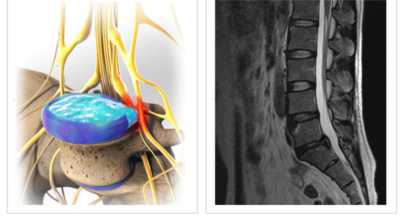

여러 개의 작은 척추뼈가 모여서 척추라는 신체의 기둥을 이루게 돼요. 척추뼈 사이에는 척추뼈끼리 부딪치는 것을 방지하는 쿠션 같은 역할을 하는 '디스크(disc)'라는 말랑말랑한 젤리 같은 구조물이 있는데 우리말로는 '추간판'이라고 합니다.

디스크(추간판)의 한가운데에는 젤리같이 찐득찐득한 '수핵'이라 하는 물질이 들어 있어요. 그 주변에 수핵을 둘러싸는 '섬유륜'이라 하는 두꺼운 막이 있는데 디스크는 전체적으로 자동차의 타이어와 같은 형태라고 합니다.

디스크는 일어선 상태에서는 중력을 받아 납작해져서 바깥쪽으로 약간 볼록한 형태가 된다고 합니다. 디스크는 그 특수한 구조 때문에 웬만한 힘이 가해져도 효율적으로 쿠션 역할을 할 수 있겠습니다. 그러나 급작스럽게 무거운 물건을 들어 올리거나, 부자연스러운 자세를 오랜 시간 취하면 디스크에 무리한 힘이 가해지면서 디스크가 밖으로 돌출이 되게 돼요. 심한 경우 디스크를 감싼 막이 터지면서 그 안에 있는 수핵이 튀어나오게 돼요.

디스크는 대개 후방이나 후외방으로 돌출되는데 이때 바로 곁에 있는 신경을 누르게 된다고 합니다. 돌출된 디스크는 척추의 어느 부위에나 일어날 수 있어요. 목에 생기면 '목 디스크', 등에 생기면 '등 디스크', 허리에 생기면 '허리 디스크'라고 부른다고 합니다.